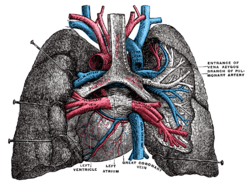

Base and diaphragmatic surface of heart. The position and relation of the esophagus in the cervical region and in the posterior mediastinum. Seen from behind.

The position and relation of the esophagus in the cervical region and in the posterior mediastinum. Seen from behind. Left atrium